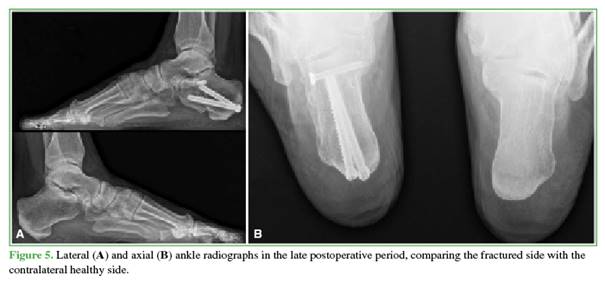

The number and orientation of the 6.5/7 mm screws will depend on the fracture lines. The objective of these screws is to support the greater tuberosity with the calcaneal body and the lesser tuberosity, also creating a “scaf-folding” that provides stability to the posterolateral articular facet (Figures 4-6).

The mean Böhler angle showed significant differences between the contralateral healthy calcaneus (30.76° ± 5.71°) and the preoperative measurement (14.05° ± 6.60°). However, the differences between the healthy side (30.76° ± 5.71°) and the postoperative values, both immediate (29.50° ± 5.96°) and remote (29.86° ± 6.51°), were minimal. The 25th, 50th, and 75th percentiles were also considered. Student’s t-tests for independent samples confirmed that there was no statistically significant difference between measurements on the healthy contralateral calcaneus and the immediate postoperative values (95% confidence interval [CI], p = 0.571, d = 0.216) or the remote values (95% CI, p = 0.700, d = 0.147), whereas there were significant differences compared to the preoperative values (95% CI, p < 0.001, d = 2.708).

The mean Gissane angle showed differences between the contralateral healthy calcaneus (119.03° ± 6.99°) and the preoperative value (110.31° ± 10.01°). However, the differences between the healthy side (119.03° ± 6.99°) and the immediate (118.85° ± 7.54°) and remote (119.00° ± 7.43°) postoperative values were not statistically significant. Student’s t-tests for independent samples confirmed that there was no statistically significant difference between the healthy contralateral calcaneus and the immediate (95% CI, p = 0.948, d = 0.0248) or remote (95% CI, p = 0.992, d = 0.004) postoperative values, while there was a significant difference compared to the preoperative values (95% CI, p = 0.013, d = 1.010).

The mean calcaneal length showed minimal differences between the contralateral healthy calcaneus (77.61 ± 8.25), the preoperative value (76.01 ± 8.47), and the immediate (78.26 ± 8.01) and remote (76.99 ± 7.56) postoperative values. Student’s t-tests for independent samples confirmed that there were no statistically significant differences between the healthy contralateral calcaneus and the preoperative value (95% CI, p = 0.617, d = 0.191), the immediate (95% CI, p = 0.835, d = –0.080), or the remote (95% CI, p = 0.836, d = 0.078) postoperative values.

The mean calcaneal width showed differences between the contralateral healthy calcaneus (36.94 ± 4.09) and the preoperative value (44.13 ± 9.36). However, the differences between the healthy side (36.94 ± 4.09°) and the immediate (39.17 ± 4.77) and remote (38.99 ± 5.16) postoperative values were minimal.

Postoperative CT scans revealed 9 anatomic reductions and 5 near-anatomic reductions.

Although the ELA offers better fracture exposure and should theoretically yield superior reductions, STA with cannulated screws has been shown to be more reliable in restoring Gissane and Böhler angles. Pitts et al.23 compared 51 DIACFs treated with STA and cannulated screws to 23 treated with ELA and found no significant differences. Wang et al.21 argue that cannulated screws ensure better reductions In our series, postoperative Gissane and Böhler angles were not significantly different from the contralateral healthy calcaneus, suggesting that limited exposure does not compromise reduction quality. Sanders et al. recommend CT imaging to evaluate postoperative PLAF reduction and classify outcomes based on the residual step height: reductions are considered anatomic when the step is ≤1 mm and near-anatomic when it measures between 1 and 3 mm.6 In our series, STA enabled us to achieve 9 anatomic and 5 near-anatomic reductions; no steps >2 mm were recorded. We believe that the visualization of the PLAF provided by the STA is sufficient for adequate reduction.